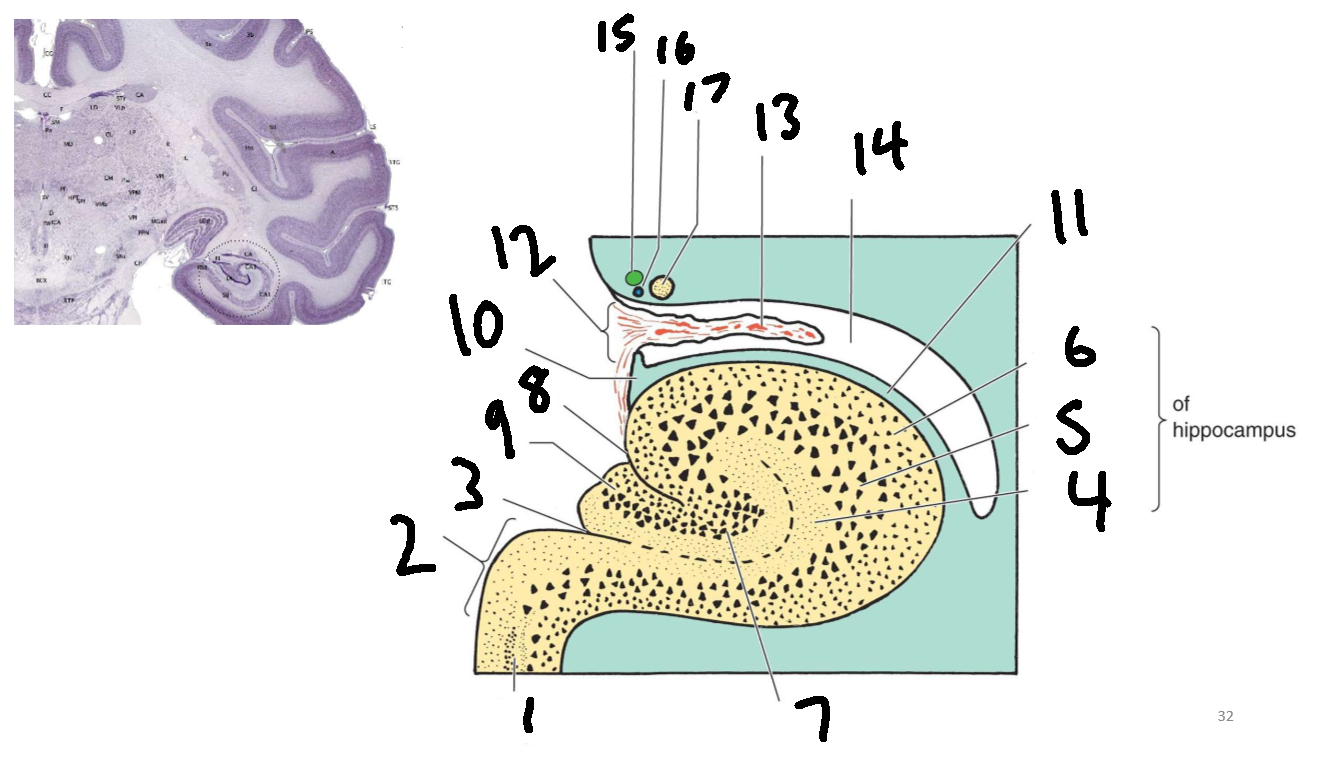

What is 1?

parahippocampal gyrus

What is 2?

subiculum

What is 3?

hippocampal sulcus

What is 4?

molecular layer

What is 5?

pyramidal layer

What is 6?

polymorphic cell layer

What is 7?

granule cell layer of dentate gyrus

What is 8?

fimbriodentate sulcus

What is 9?

dentate gyrus

What is 10?

fimbria of hippocampus

What is 11?

alveus

What is 12?

choroid fissure

What is 13?

choroid plexus

What is 14?

temporal horn of lateral ventricle

What is 15?

stria terminalis

What is 16?

thalamostriate vein

What is 17?

tail of caudate nucleus